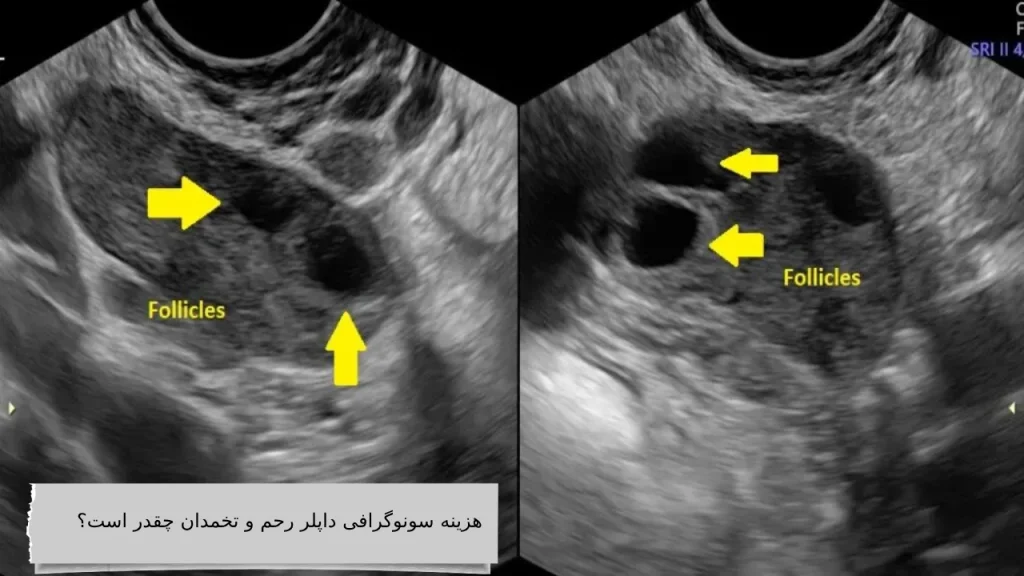

سونوگرافی داپلر رحم و تخمدان یکی از روشهای پیشرفته تصویربرداری است که به کمک آن میتوان جریان خون در عروق ناحیه لگن، بهویژه در رحم و تخمدانها را بررسی کرد. این روش معمولاً زمانی تجویز میشود که پزشک به مشکلاتی مانند کاهش یا افزایش جریان خون، وجود توده یا کیست، فیبروم، سندرم تخمدان پلیکیستیک (PCOS)، یا اختلالات مربوط به باروری مشکوک باشد.

هزینه سونوگرافی داپلر رحم و تخمدان یکی از سوالات رایج در میان افرادی است که نیاز به بررسی دقیقتر سلامت دستگاه تناسلی زنان دارند. این نوع سونوگرافی با استفاده از امواج صوتی، جریان خون در رگهای رحم و تخمدان را بررسی میکند و در تشخیص مشکلاتی مانند کیست، فیبروم، ناهنجاریهای عروقی یا ناباروری بسیار مؤثر است. هزینه سونوگرافی داپلر رحم و تخمدان بسته به نوع مرکز درمانی (خصوصی یا دولتی)، موقعیت جغرافیایی، نوع دستگاه و تخصص پزشک متفاوت است، اما به طور میانگین بین ۳۰۰ تا ۷۰۰ هزار تومان برآورد میشود.